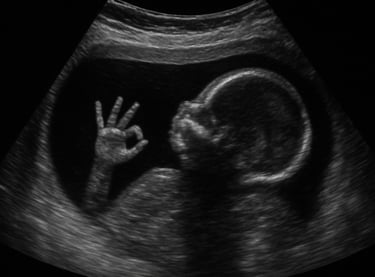

Le Spina Bifida est une malformation du tube neural, structure embryonnaire qui donnera naissance à la moelle épinière.

Elle se traduit par une fermeture incomplète de la colonne vertébrale, provoquant des troubles moteurs, urinaires et neurologiques variables selon la gravité de la lésion.